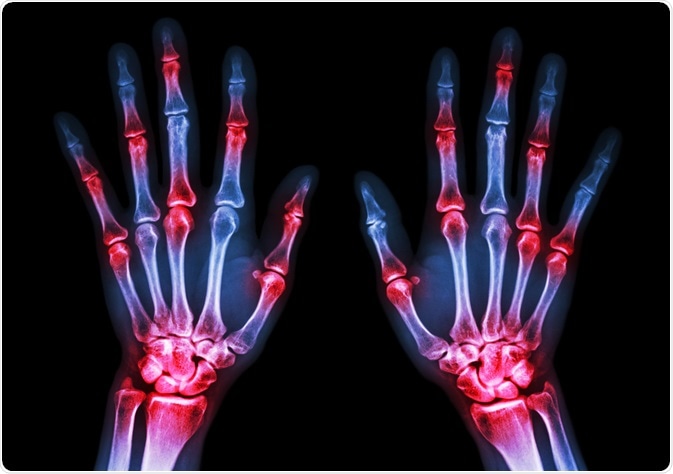

arthritisImage Credit: Puwadol Jaturawutthichai / Shutterstock.com

Rheumatoid arthritis (RA) is an autoimmune disorder that causes inflammation of the joints. RA is a chronic and progressive condition that causes debilitating effects on the patient. The condition is characterized by pain and stiff joints.

Another typical feature of this disorder is bone and joint destruction and the presence of autoantibodies in the serum and synovial fluid. Synovial fluid is the fluid that lubricates the synovial joints.